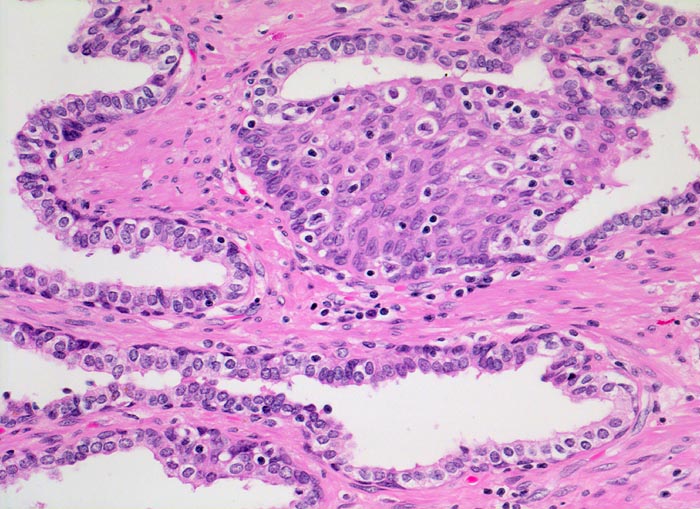

Das normale Prostataparenchym besteht aus Paketen grösserer Drüsen eingebettet in glatte Muskulatur. Das Epithel der tubuloalveolären Drüsen ist ein- bis mehrreihig und weist eine durchgehende Schicht flachgedrückter Basalzellen auf. Nicht selten kann eine fokale Hyperplasie dieser Zellen nachgewiesen werden. Die Epithelzellen haben mittelgrosse runde bis ovale Kerne mit winzigen Nukleolen und reichlich Zytoplasma.

Die Abwesenheit der Basalzellschicht ist eines der verlässlichsten Kriterien zur Diagnose eines Adenokarzinoms. In verschiedenen benignen Läsionen ist die Basalzellschicht fragmentiert, fehlt aber praktisch nie vollständig. In Zweifelsfällen kann die Basalzellschicht immunhistochemisch nachgewiesen werden.